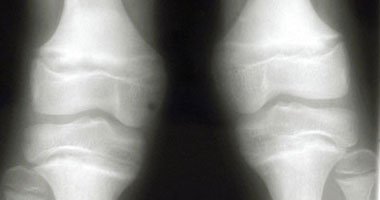

استخدام أنسجة من جسم المريض يرفع فرص نجاح جراحات الرباط الصليبى